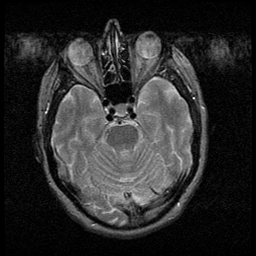

Huntington's Chorea, MR -- Slice #5

[Home][Help][Clinical] Slice 5